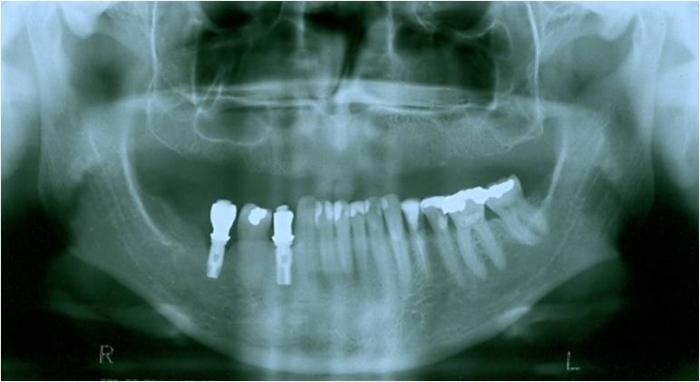

Raio x após enxerto de ilíaco